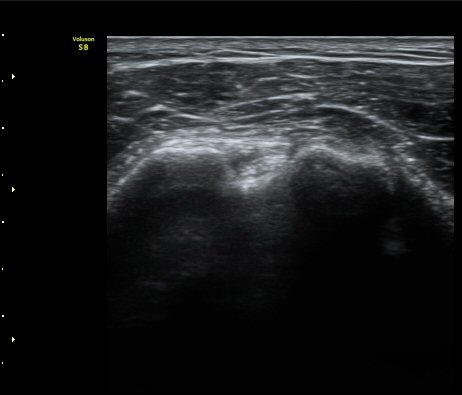

¿ÜȸÀüÀÇ Á¦ÇÑÀ¸·Î °ß°©ÇϱٰÇÀÌ ¼öÆòÀ¸·Î °üÂûµÇÁö ¸øÇϰí À̵ιڱ٠ǥÃþ¿¡

¼®È¸È­ À½¿µÀÌ °üÂûµÊ(±×¸² 3)